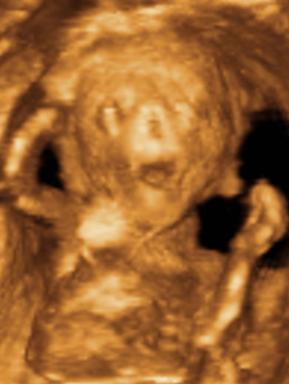

Ui.: Kedden megyünk genetikai UH-ra, szorítsatok nekem. Aztán majd jelentkezem.